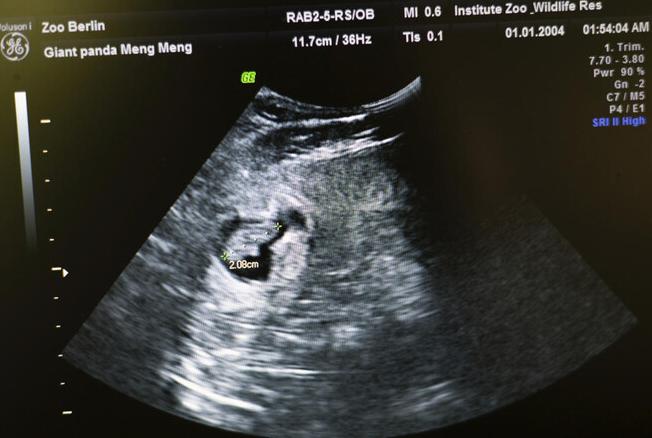

The cubs were born on Thursday and are doing well, the zoo said in a statement. They were born only 11 days after ultrasound scans showed that Meng Meng, 11, was pregnant. Their sex has not yet been determined “with certainty.”